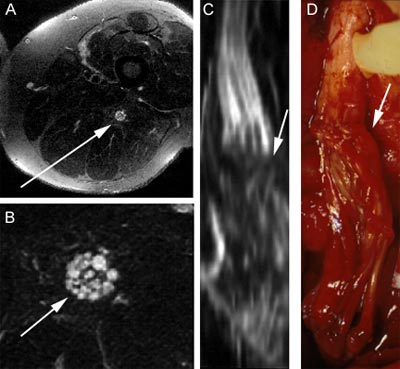

Dr. Aaron Filler's pulse-sequence innovation, which created modern MR neurography, had its first major test in November 1992, using a Signa general clinical magnetic resonance scanner. The scan below highlights the sciatic nerve structure while all other surrounding tissues stay dark. This was the first image that demonstrated the ability to capture the fascile pattern within the nerve; It was also the first image to prove that the highlighted structure was indeed a nerve.

A - Thigh cross section. The arrow indicates the sciatic nerve. This patient had suffered a stab wound to the thigh that had severed his sciatic nerve.

B - Expanded view of the sciatic nerve revealing the internal structure of the fascicle.

C - Three-dimensional reconstruction of the nerve based on the "maximum intensity projection" of the nerve. This image closely matches the shape of the sciatic nerve seen in the resonance image.

D - Intraoperative photograph taken during surgery. The photo shows the severed sciatic nerve. The arrow indicates the suture line where the grafts of

nerve were seeded in place.